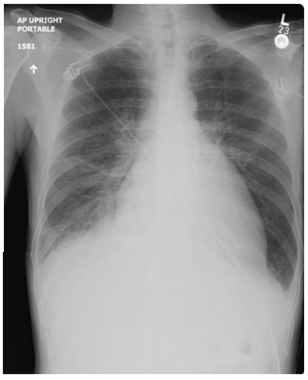

Um homem de 64 anos de idade, com história de infarto agudo do miocárdio extenso em parede anterior, com colocação de stent farmacológico há seis semanas, retornou ao consultório médico com queixa de dor precordial, em opressão, ventilatório-dependente, melhorando com decúbito. Refere uso correto de medicações. Ao exame: PA de 120 x 70 mmHg, bilateral; FC de 61 bpm; FR de 21 ipm; temperatura de 38,6 ⁰C; BRNF em 2T, sem sopros audíveis; presença de atrito pericárdico e pleural, sem edemas. No exame laboratorial: hemoglobina 14,8 mg/dL; leucócitos 10.200; plaquetas 420.000; troponina < 0,001; PCR 19; e VHS 50 mm/h.